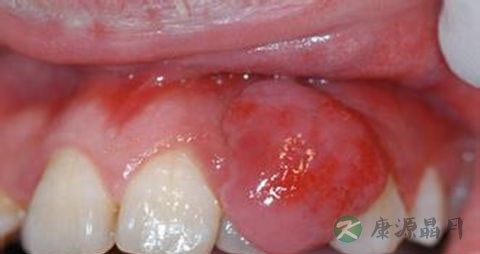

牙龈呈深红色或暗红色,肿胀肥大,龈缘圆钝,牙龈乳头呈球状。组织松软,探诊易出血,也可有脓性分泌物。严重者附着龈可因组织水肿,点彩消失,表面光亮,龈缘可有糜烂或肉芽增生,龈袋溢脓。急性牙周脓肿发病突然,牙龈红肿光亮,患处牙龈形成椭圆形或半球状的肿胀突起,未成熟时张力大,疼痛较明显,成熟后有波动感。

患牙因牙周膜水肿而有“浮起感”,叩痛,松动明显。脓肿后期,脓液局限,脓肿表面较软,检查可见溢脓。可有局部淋巴结肿大,或有白细胞轻度增高。脓肿可自行破溃而消退。

若身体抵抗力降低时,可出现单发或多发性的龈脓肿,特别以龈乳头区较多见。若慢性牙周炎急性发作引起的牙周肿痛可伴牙齿松动。若是急性根尖周炎引起的牙龈肿痛可多可查及龋坏、隐裂等,并可有牙齿浮出感。牙龈肿痛患者多伴有牙龈出血、自觉牙龈发胀、口臭等。

引起牙龈肿痛的原因主要包括牙龈脓肿、牙周脓肿、智齿冠周炎或根尖周炎等,最为常见是牙周脓肿引起的病症,年轻人多见智齿冠周炎。